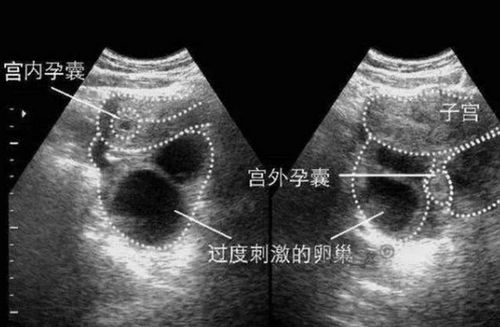

超声波检查:通过超声波检查子宫和输卵管,寻找胚胎的位置。